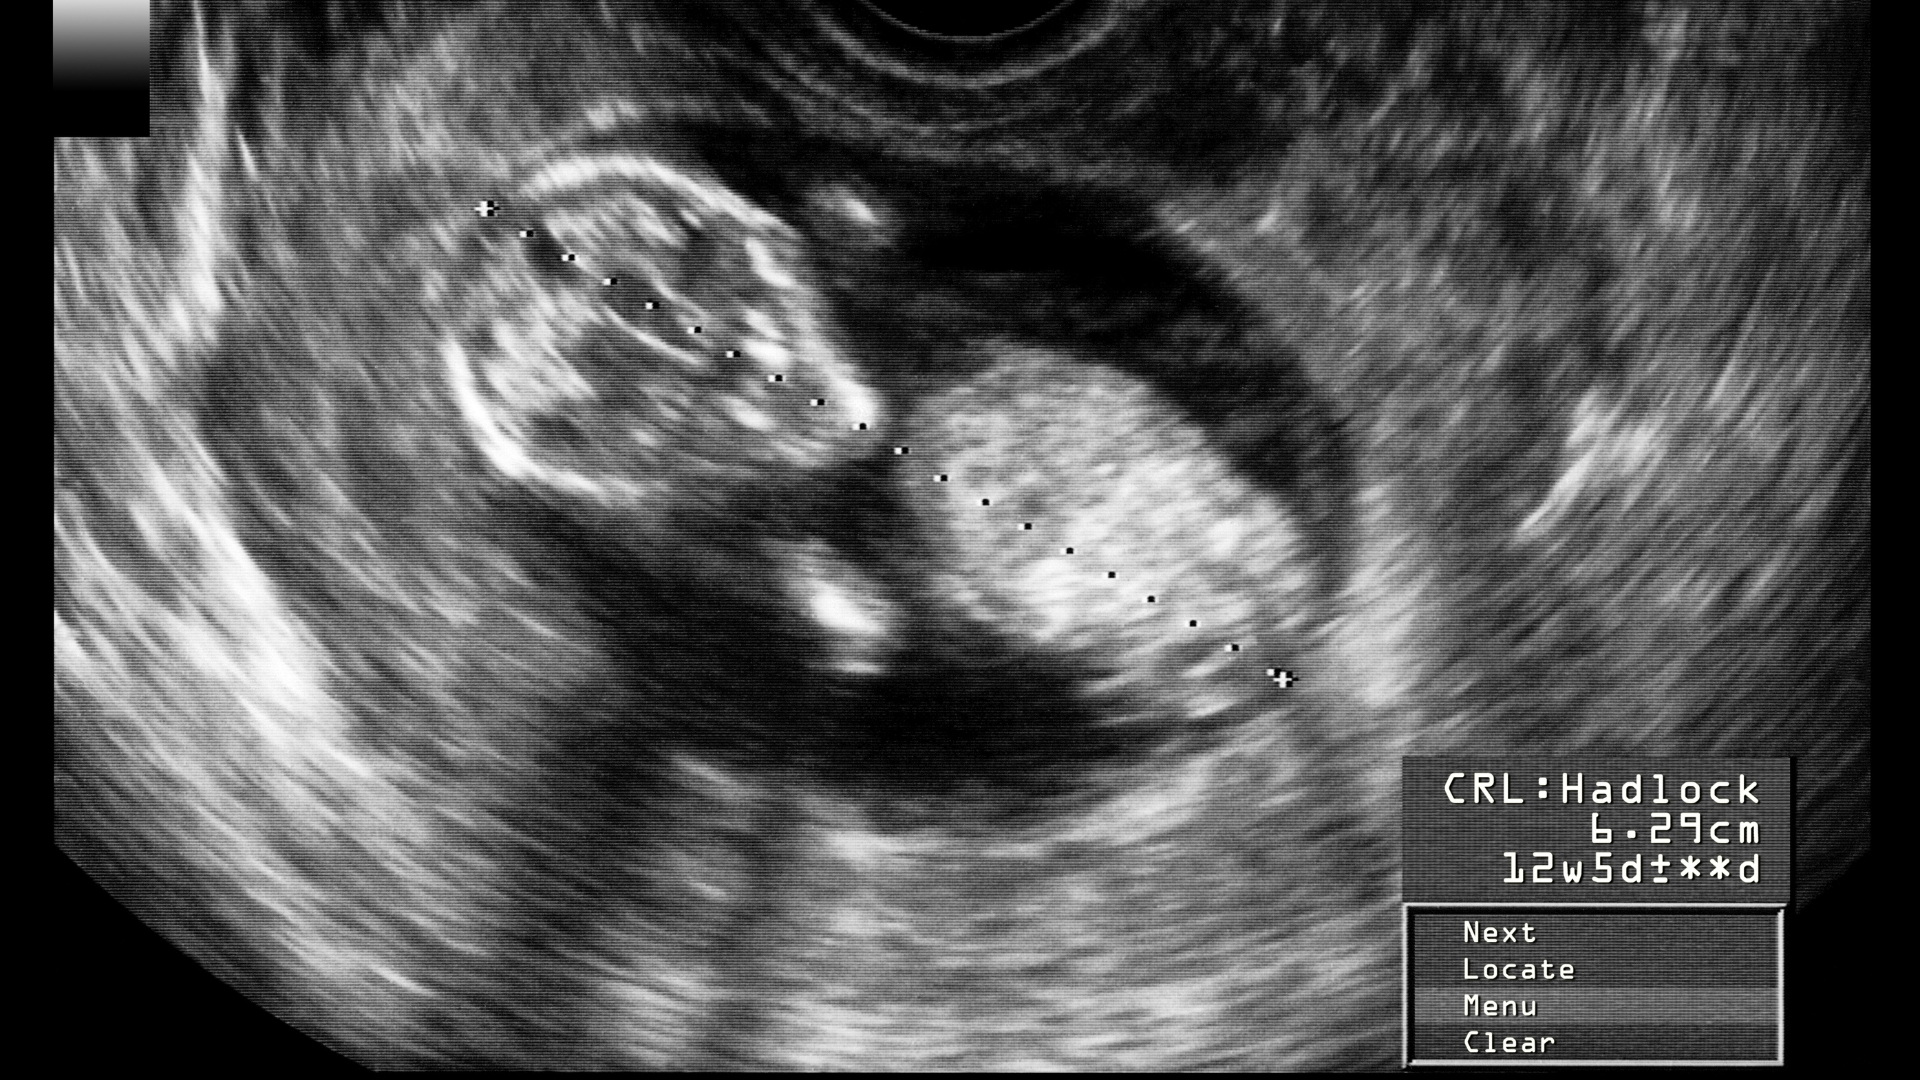

Đến bệnh viện ngay: Bác sĩ sẽ thăm khám, làm xét nghiệm dịch và siêu âm để đánh giá lượng ối.